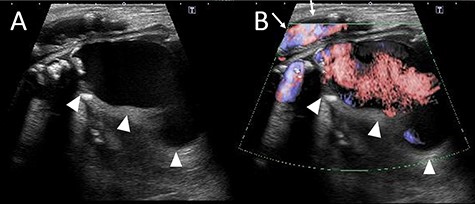

The patient looked pale but was conscious. He was thin and weighed 40 kg (body mass index, 14.5) due to loss of appetite after gastric surgery; however, his left thigh was reddish, edematous and painful (Fig. 1). Hemodynamics, such as blood pressure and heart rate, were stable. Blood tests revealed a hemoglobin level of 3.41 mmol/l. Ultrasonography showed a 72 × 52 mm PFAA with a thick thrombus and hematoma extending into the adductors (Fig. 2). A venous thrombus was also observed in the left femoral vein. Enhanced computed tomography (CT) revealed a ruptured left PFAA 64 × 54 mm in diameter (Fig. 3A and C). In addition, right iliac artery aneurysm and right CFA and SFA occlusion were also observed.

(A) The ultrasound image. The deltas point the PFAA. (B) Color Doppler imaging using ultrasonography. The deltas indicate the PFAA, and the arrows indicate the blood flow of the SFA.